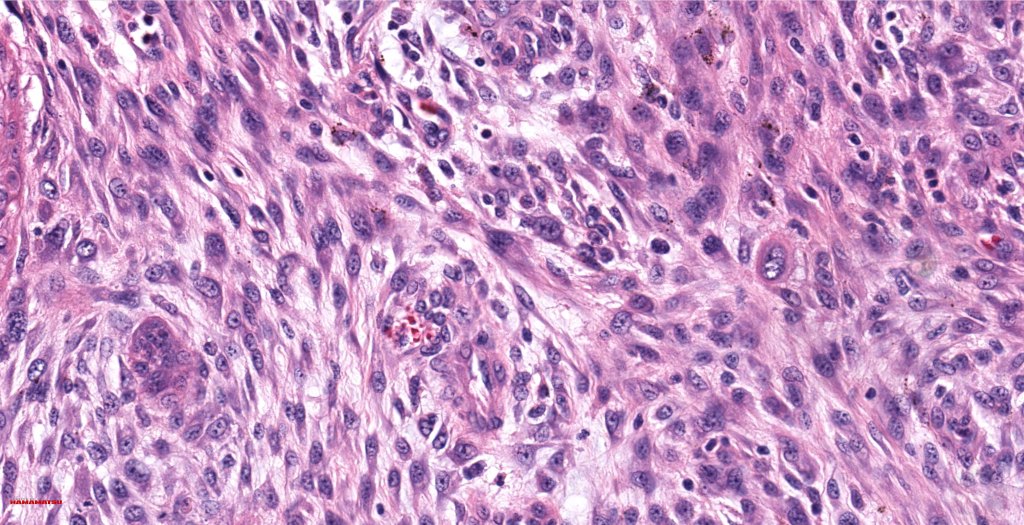

•Admixture of squamous carcinoma & pleomorphic spindled cell, osteoid, chondroid, MFH-like +/- osteoclast-like giant cells & rarely, smooth muscle, skeletal muscle, myofibroblastic or angiosarcomatous elements

•Epithelial component AE1/AE3, CK5/6 & p63 +ve;

•Mesenchymal element variable CD10, CD68, CD99 & lineage specific markers +ve; scattered cells may show weak keratin expression